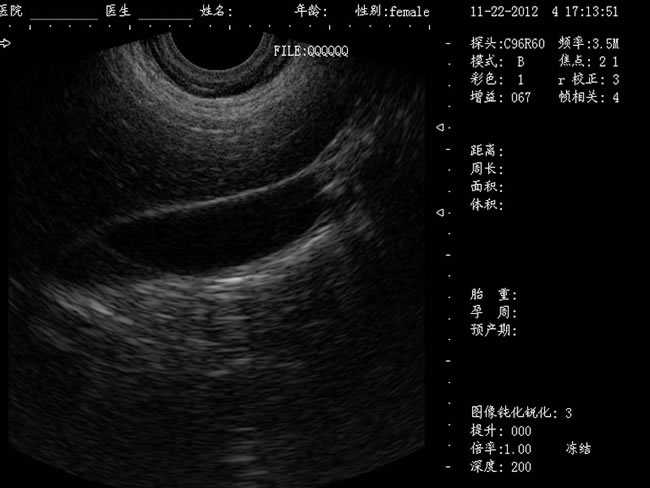

超聲婦產科手術監視儀-可視人流機

DW-CE780推車式全數字彩色多普勒超聲診斷儀

DW-400

定位精確 手術效率高:實時動態頻率掃描等全數字超聲成像技術、生成精確的圖像引導手術器械迅速到大手術位置,避免損傷子宮內膜和子宮穿孔的現象,即減輕了患者的痛苦又極大提高了手術效率。

CXA10R/6.5MHz 腔內探頭

選配:CXA60R/3.5MHz 凸陣探頭

隨著醫療技術水平的提高,目前婦產科手術中所應用的相關設備也有了加大的改進。尤其是在人工流產手術中,將B超婦產科手術監視儀應用到手術過程中,彌補傳統手術中所采用設備的不足之處,減輕手術中患者的疼痛感覺,使得手術順利的完成。這種儀器相比于傳統的儀器來說,其在操作上更為方便和簡單,能夠對妊娠反應有很好的療效。